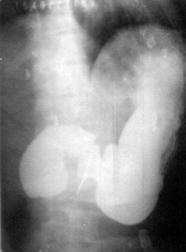

Semnele pentru ulcer apar la nivelul micii curburi si in regiunea cardiei si bulbul duodenal. Semnul de certitudine este nisa, o umbra in plus data de bariul ingerat. In absenta nisei se cauta semne radiologice indirecte: pliuri convergente ale mucoasei spre nisa, spasme persistente, tranzit bulbar accelerat.

Daca durerea este semnul clinic cardinal, nisa ca semn direct are aceeasi importanta in diagnosticul radiologic. Expresie a substantei baritate la nivelul ulceratiei, nisa poate imbraca aspecte diferite in functie de localizare (curburi, fete), dimensiuni si profunzime. Localizata cel mai ades pe mica curbura este vazuta din profil "in afara conturului gastric", ceea ce o diferentiaza de nisa maligna (incastrata, dispusa in conturul gastric).

Morfologic nisa de profil (curbura) poate sa apara sub mai multe forme: nisa mica triunghiulara sub forma unui spicul; nisa de talie medie cu sau fara halou clar in jur; nisa pediculara, care apare ca un diverticul la nivelul micii curburi, legat de stomac printr-un pedicul subtire (are intotdeauna semnificatia unui ulcer penetrant); nisa Haudek tipica cu cele 3 nivele (bariu lichid de secretie si aer, proprie numai ulcerului gastric); nisa giganta, al carui diametru depaseste 5 cm care este de obicei expresia unei penetratii vechi cu distructia peretelui gastric, astfel incat fundul ulcerului este constituit din parenchimul organului penetrat (ficat, pancreas, regiunea celiaca). Astfel de nise se intalnesc la oameni varstnici si apar pe fondul unor defecte importante de irigatie (pe fond ateromatos), ridicand mari probleme de diagnostic diferential cu cancerul.

Rx cu bariu